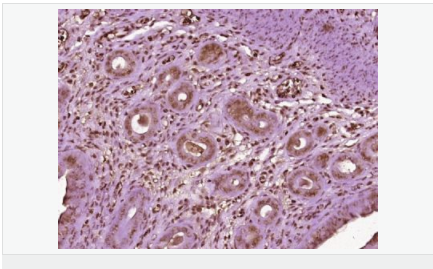

| 產(chǎn)品應(yīng)用 | WB=1:500-2000 IHC-P=1:100-500 IHC-F=1:100-500 Flow-Cyt=1ug/Test ICC=1:100-500 IF=1:100-500 (石蠟切片需做抗原修復(fù)) not yet tested in other applications. optimal dilutions/concentrations should be determined by the end user. |

| 細胞定位 | 細胞核 細胞漿 |

| 產(chǎn)品介紹 | Estrogen and progesterone receptor are members of a family of transcription factors that are regulated by the binding of their cognate ligands. The interaction of hormone-bound estrogen receptors with estrogen responsive elements(EREs) alters transcription of ERE-containing genes. The carboxy terminal region of the estrgen receptor contains the ligand binding domain, the amino terminus serves as the transactivation domain, and the DNA binding domain is centrally located. Two forms of estrogen receptor have been identified, ER alpha and ER beta. ER alpha and ER beta have been shown to be differentially activated by various ligands. The biological response to progesterone is mediated by two distinct forms of the human progesterone receptor (hPR-Aand hPR-B), which arise from alternative splicing. In most cells, hPR-B functions as a transcriptional activator of progesterone-responsive gene, whereas hPR-A function as a transcriptional inhibitor of all steroid hormone receptors. Function: The steroid hormones and their receptors are involved in the regulation of eukaryotic gene expression and affect cellular proliferation and differentiation in target tissues. Progesterone receptor isoform B (PRB) is involved activation of c-SRC/MAPK signaling on hormone stimulation. Isoform A is inactive in stimulating c-Src/MAPK signaling on hormone stimulation. Subunit: Interacts with SMARD1 and UNC45A. Interacts with CUEDC2; the interaction promotes ubiquitination, decreases sumoylation, and repesses transcriptional activity. Interacts with PIAS3; the interaction promotes sumoylation of PR in a hormone-dependent manner, inhibits DNA-binding, and alters nuclear export. Interacts with SP1; the interaction requires ligand-induced phosphorylation on Ser-345 by ERK1/2 MAPK. Interacts with PRMT2. Subcellular Location: Nucleus. Cytoplasm. Note=Nucleoplasmic shuttling is both homone- and cell cycle-dependent. On hormone stimulation, retained in the cytoplasm in the G(1) and G(2)/M phases. Isoform A: Nucleus. Cytoplasm. Note=Mainly nuclear. Post-translational modifications: Phosphorylated on multiple serine sites. Several of these sites are hormone-dependent. Phosphorylation on Ser-294 occurs preferentially on isoform B, is highly hormone-dependent and modulates ubiquitination and sumoylation on Lys-388. Phosphorylation on Ser-102 and Ser-345 also requires induction by hormone. Basal phosphorylation on Ser-81, Ser-162, Ser-190 and Ser-400 is increased in response to progesterone and can be phosphorylated in vitro by the CDK2-A1 complex. Increased levels of phosphorylation on Ser-400 also in the presence of EGF, heregulin, IGF, PMA and FBS. Phosphorylation at this site by CDK2 is ligand-independent, and increases nuclear translocation and transcriptional activity. Phosphorylation at Ser-162 and Ser-294, but not at Ser-190, is impaired during the G(2)/M phase of the cell cycle. Phosphorylation on Ser-345 by ERK1/2 MAPK is required for interaction with SP1. Sumoylation is hormone-dependent and represses transcriptional activity. Sumoylation on all three sites is enhanced by PIAS3. Desumoylated by SENP1. Sumoylation on Lys-388, the main site of sumoylation, is repressed by ubiquitination on the same site, and modulated by phosphorylation at Ser-294. Similarity: Belongs to the nuclear hormone receptor family. NR3 subfamily. Contains 1 nuclear receptor DNA-binding domain. SWISS: P06401 Gene ID: 5241 Database links: Entrez Gene: 5241 Human Entrez Gene: 18667 Mouse Entrez Gene: 100009094 Rabbit Omim: 607311 Human SwissProt: P06401 Human SwissProt: Q00175 Mouse SwissProt: P06186 Rabbit Unigene: 2905 Human Unigene: 32405 Human Unigene: 742403 Human Unigene: 12798 Mouse Unigene: 437703 Mouse Unigene: 1947 Rabbit Unigene: 10303 Rat Important Note: This product as supplied is intended for research use only, not for use in human, therapeutic or diagnostic applications. |